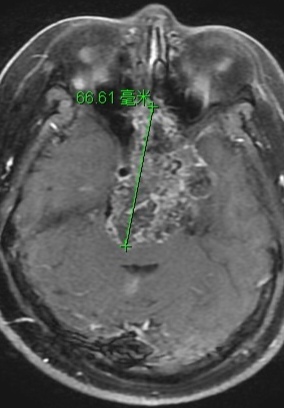

3.辅助检查:鼻咽CT增强扫描蝶骨体骨质破坏,局部形成巨大软组织肿块,内见散在钙化,前后径约64mm,左右径约47mm,左侧颞叶受压,向后压迫桥脑,向前突入筛房,前颅窝底骨质破坏。

3.诊断:软骨肉瘤?